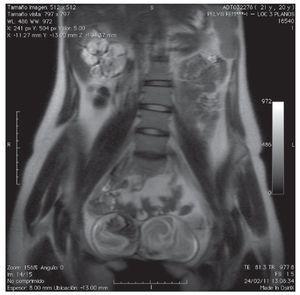

Paciente femenino de 20 años de edad, antecedente de extrofia vesical con cierre espontáneo. A la exploración física, se encuentra la presencia de duplicación de genitales internos y externos (clítoris, vaginas, útero), así como falta de fusión de la pelvis ósea (Figura 1). Paciente acudió al servicio de urología, por la presencia de dolor en el flanco derecho y una masa palpable. Se le realizó tomografía, donde se evidenció una bolsa hidronefrótica derecha y la presencia de dos vejigas con uretras independientes y un útero doble (Figuras 2 y 3). En la resonancia magnética, se pudieron identificar dos vejigas no comunicantes con interface entre las dos (Figuras 4 y 5). Se envió a genética reportándose cariotipo de 46XX. Se realizó cistografía, donde se evidenció la presencia de duplicación vesical completa y presencia de reflujo vesicoureteral derecho grado IV. Se realizó cistoscopia con lente pediátrico de 30 grados, observando en la uretra derecha hemivejiga con meato ureteral ortotópico dilatado, sin visualizarse el izquierdo, ni conexión a hemivejiga izquierda. Se realizó el mismo procedimiento en la uretra izquierda, visualizando uréter ortotópico y eyaculante. Se diagnosticó doble sistema genitourinario completo, con reflujo vesicoureteral grado IV y exclusión renal derecha. Se programó para nefroureterocistectomía derecha.

Figura 4. En la resonancia magnética se pudieron identificar dos vejigas no comunicantes con interface entre ellas.

Figura 5. Otra proyección de la resonancia magnética. Se identifican dos vejigas no comunicantes con interface entre ambas.